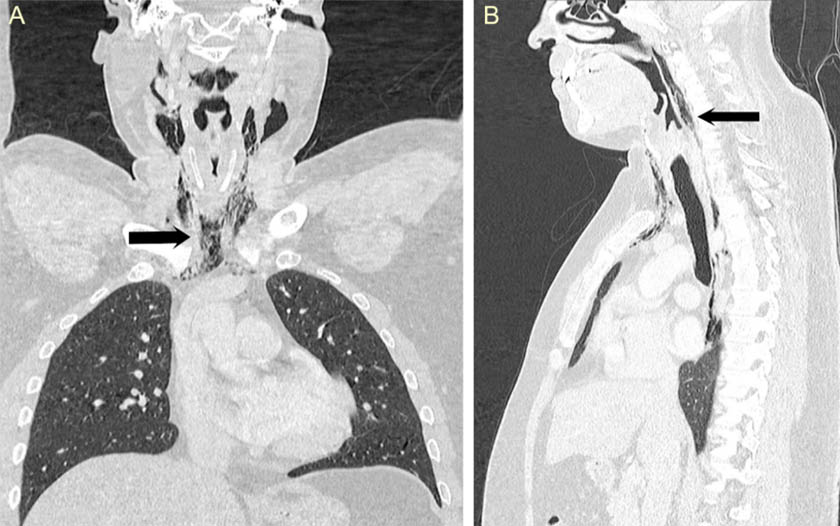

Під час обстеження медики не виявили жодних відхилень в легенях, тому зробили рентгенівський знімок і комп’ютерну томографію. Завдяки знімкам виявили, що в шиї і грудній клітці пацієнта є велика емфізема – скупчення повітря там, де його бути не повинно. Діагноз був такий: спонтанний розрив стравоходу.

КТ (пациента). Стрелки указывают на эмфиземы. Credit: Wanding Yang et al., BMJ Case Reports, 2018